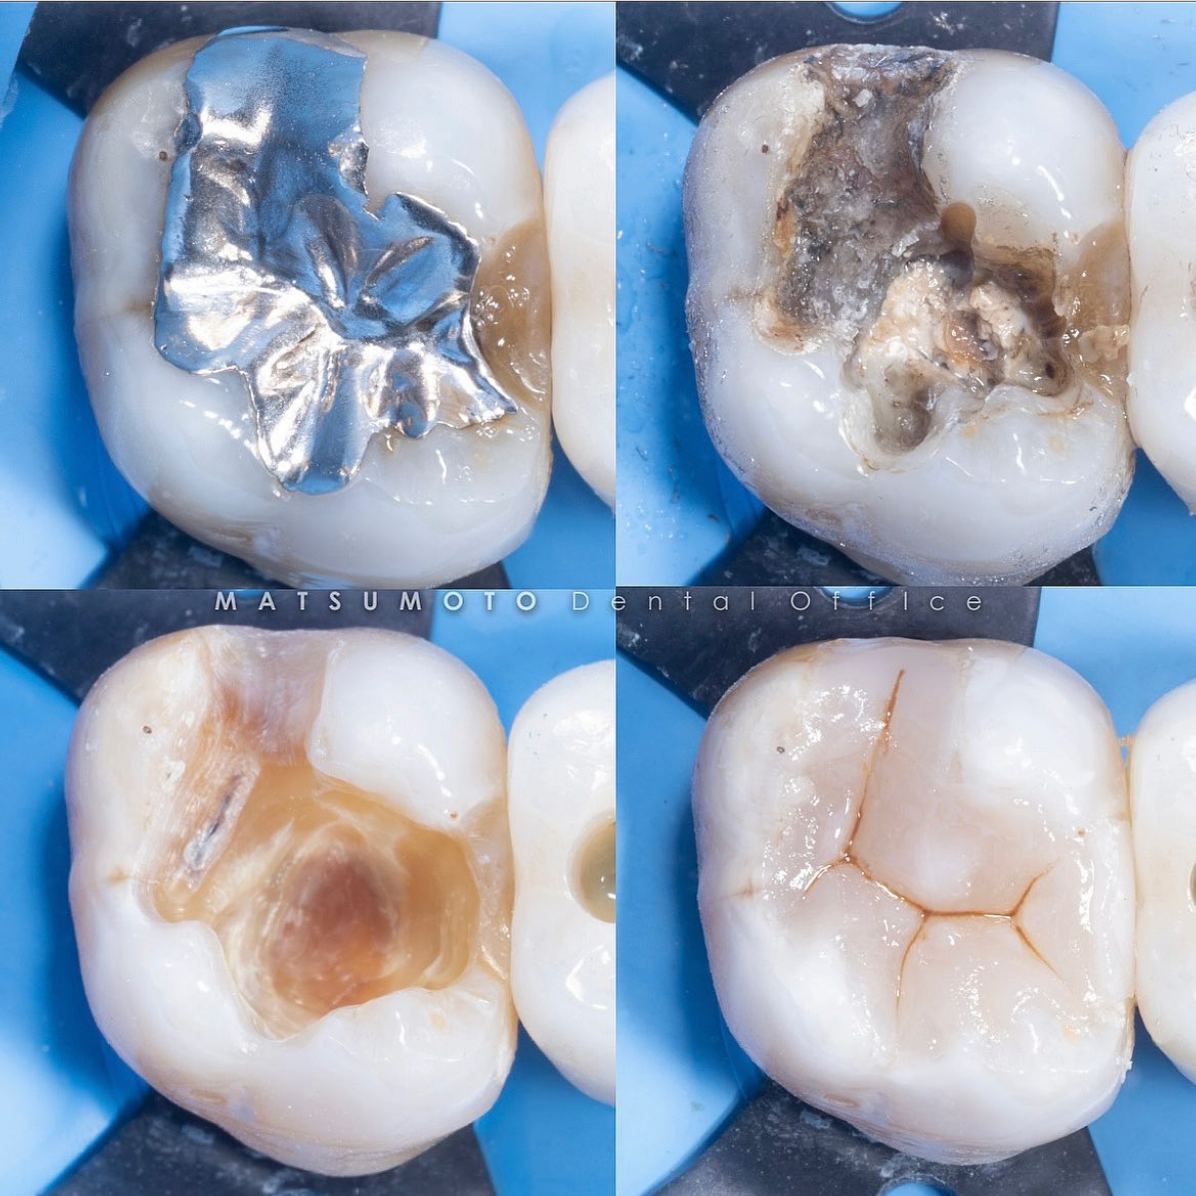

《治療名》

ダイレクトボンディング

不適合な銀歯を除去し、樹脂で治療を行いました。

ラバーダム防湿を行うことにより、より接着力が増して長期的に良好な予後を期待できます。

¥44,000(税込)

《リスク》

セラミックに比べ、磨耗しやすいですが、症例を選べば長期的にもたせることができます^_^